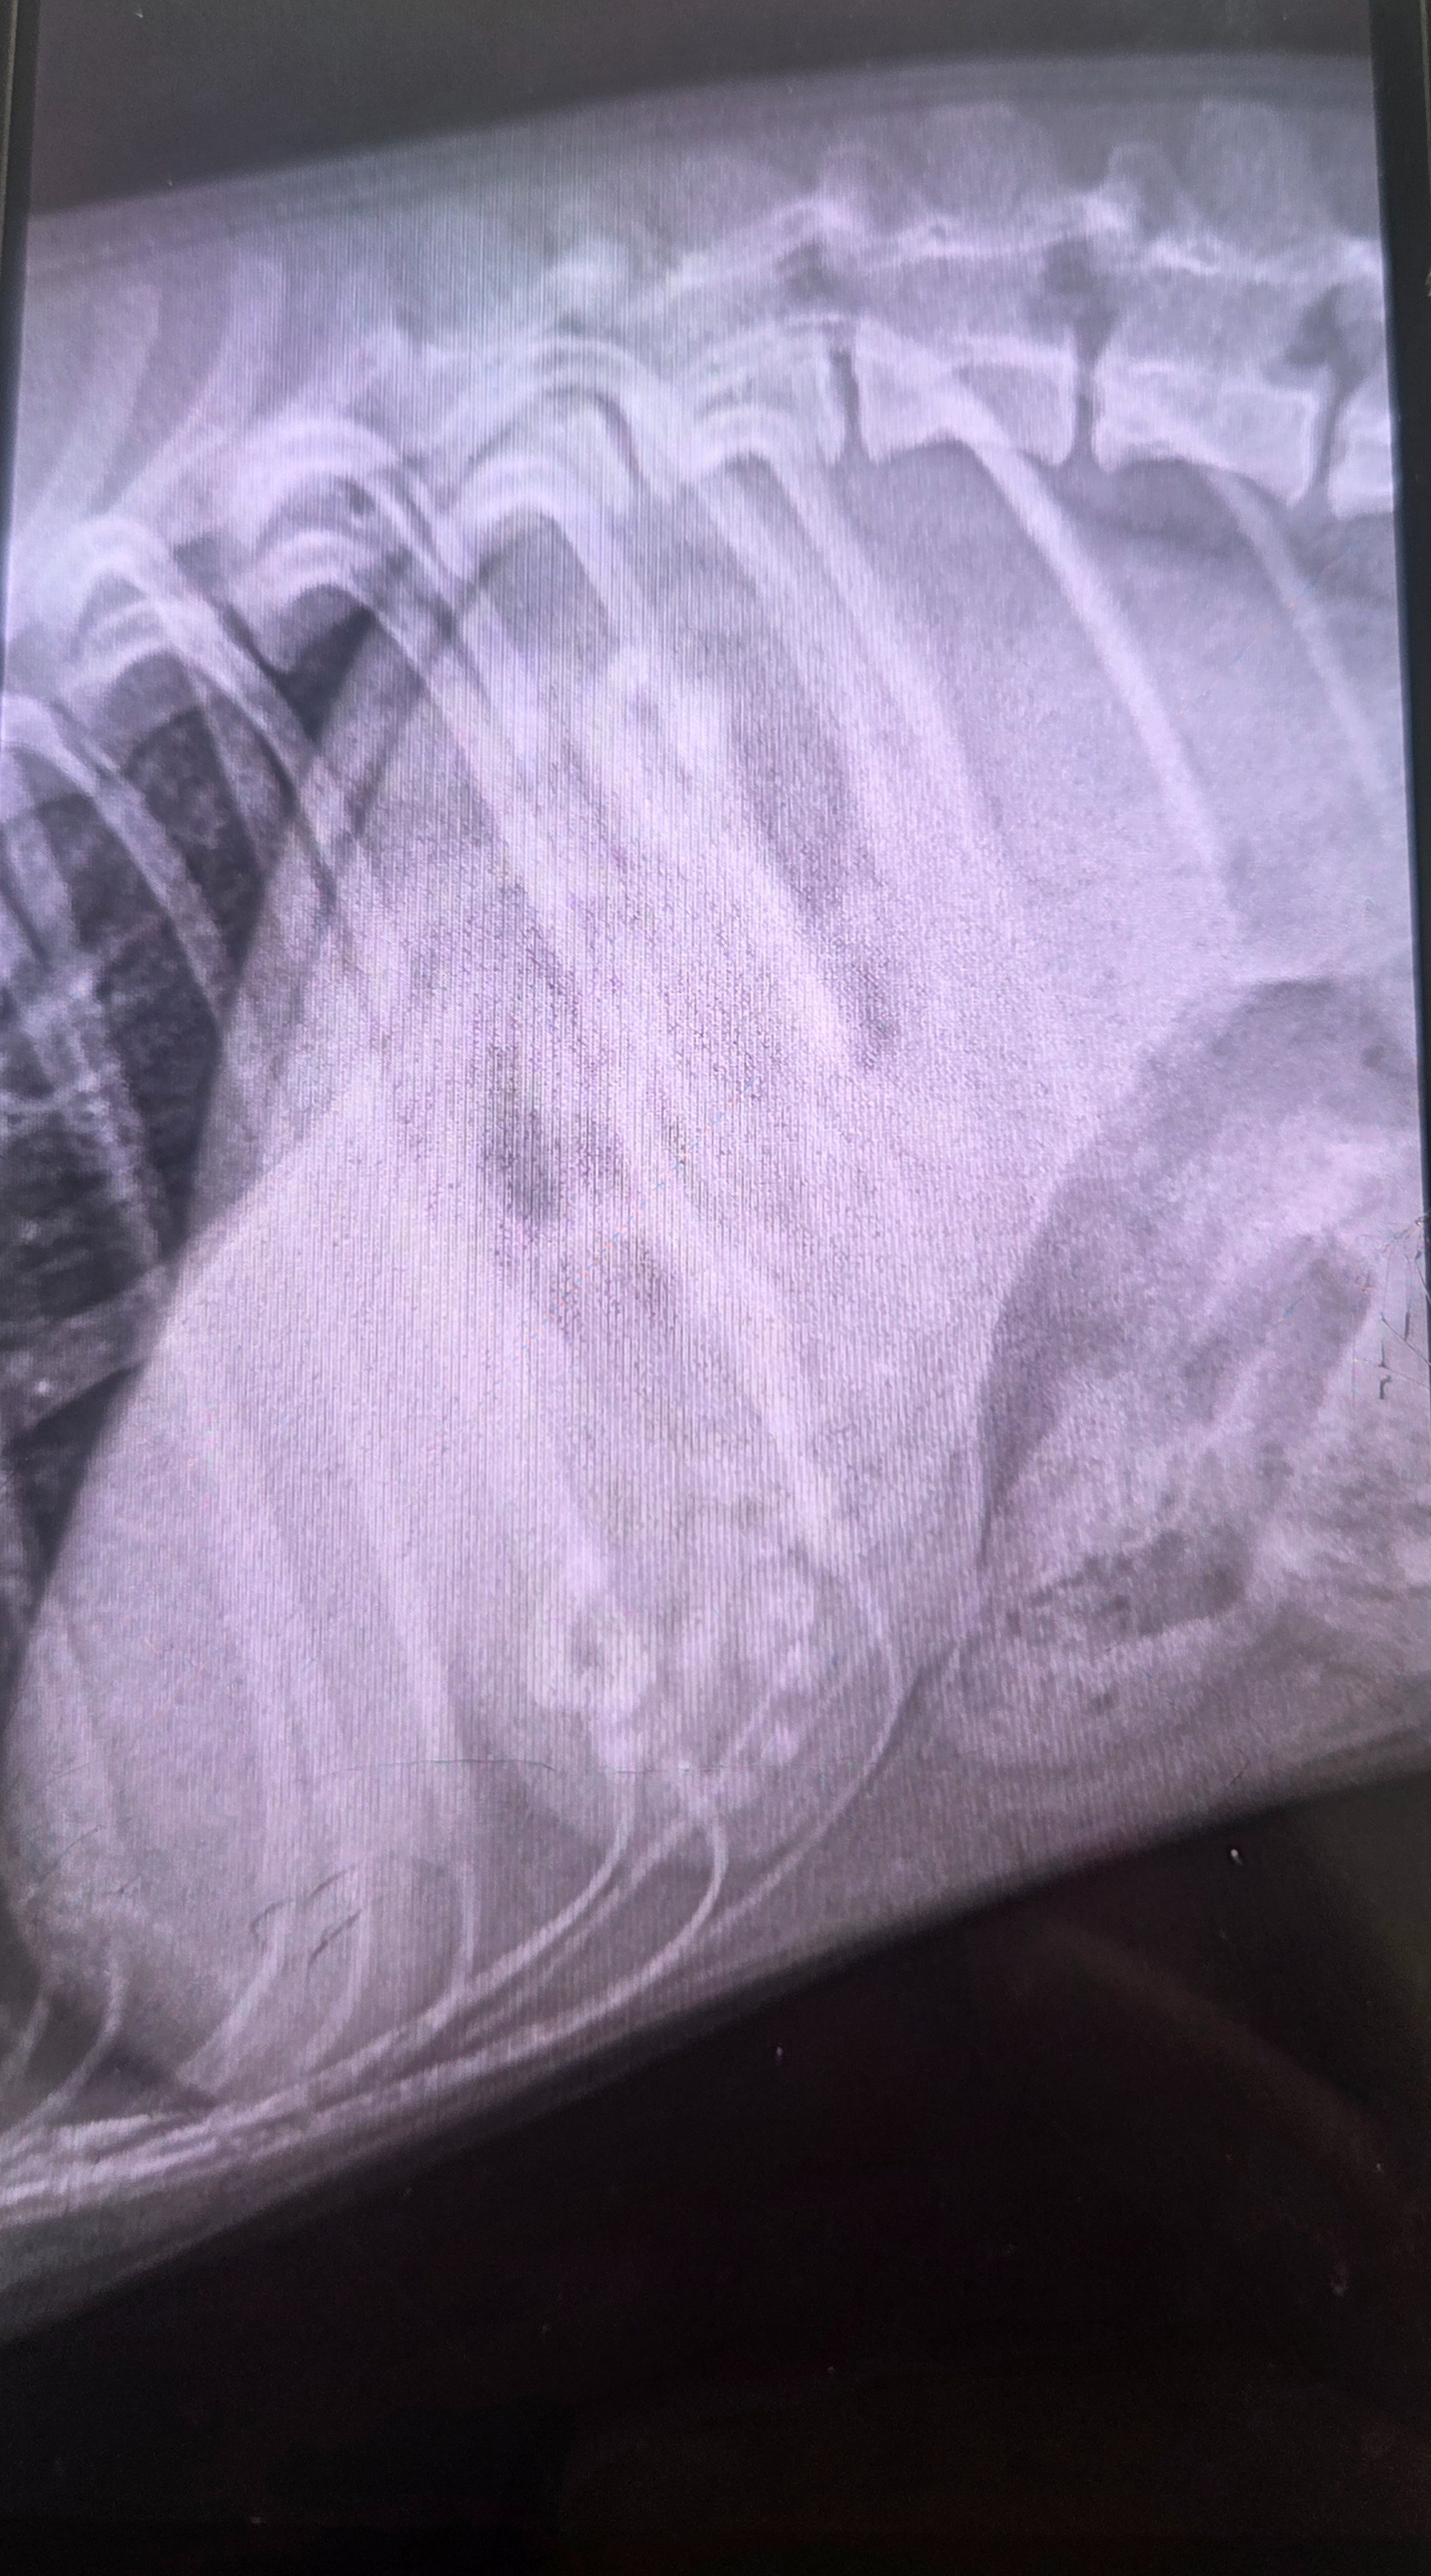

Moon swallowed a foreign object that caused a dangerous blockage in his stomach. The veterinarian confirmed this is life-threatening, and that emergency surgery is the only way to save his life.